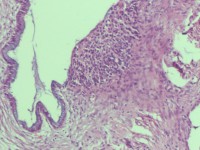

性别

女

年龄

43岁

临床诊断

宫颈病变

一般病史

宫颈癌筛查:hpv16(+))

标本名称

宫颈组织

大体所见

灰白色组织

老师们看看,高级别累腺吗

图1

高级别累腺,不除外局灶早期浸润

高级别累及腺体